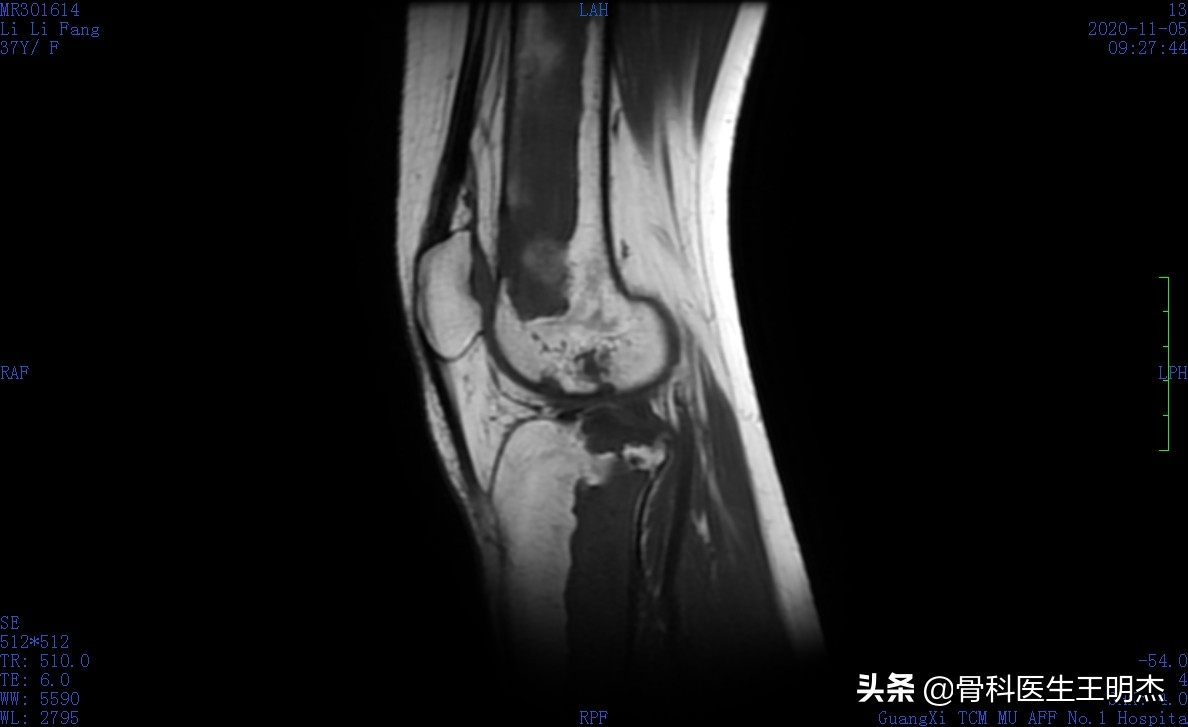

骨梗死又称骨髓梗死、骨脂肪梗死, 指发生于干骺端和骨干的骨性坏死, 多发生于股骨下端、胫骨上端和肱骨上端, 呈多发性和对称性改变。

临床上, 骨梗死可分为两种类型: (1) 单纯骨干及干骺端型骨梗死; (2) 骨干骨梗死合并关节面骨坏死 (以膝关节常见) 。

骨梗死发生后则进入骨修复阶段, 包括血管再生、肉芽组织生成、死骨吸收、新生骨形成。血管再生是骨修复的开始, 死骨吸收, 形成纤维结缔组织和致密新生骨则是骨梗死的晚期阶段。骨梗死在演变的过程中有3个基本病理改变, 即死骨块、吸收带 (充血、水肿带) 、新生骨带, 是骨梗死X线、CT、MRI等影像学诊断的基础。